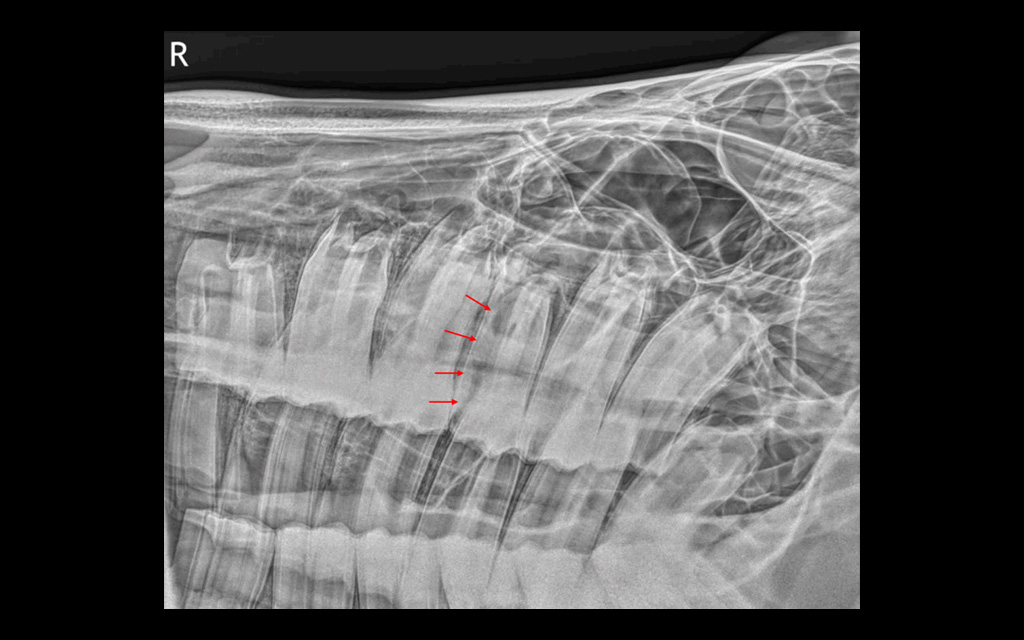

Radiograph, lateral view, tooth 109, buccal root shortening, irregular structure, alveolar sclerosis

Radiographs showed abnormal pulp horns, an occlusal fissure, root shortening, and alveolar sclerosis, while CT revealed mucosal thickening in the maxillary sinuses, buccal wall discontinuity, and gas inclusions in the periodontal space and pulp chamber.